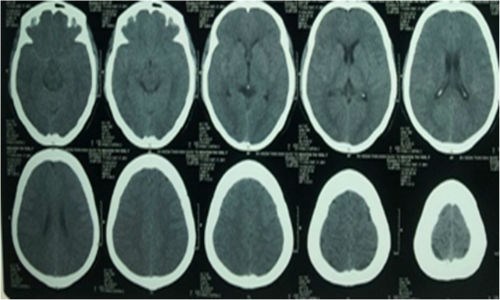

Hình ảnh chụp DSA xuất huyết dưới nhện trên bệnh nhân đa túi phình mạch não. Ảnh: Infonet.